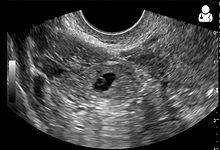

An ultrasound showing a gestational sac with fetal heart in the fallopian tube has a very high specificity of ectopic pregnancy. Transvaginal ultrasonography has a sensitivity of at least 90% for ectopic pregnancy.[4] The diagnostic ultrasonographic finding in ectopic pregnancy is an adnexal mass that moves separately from the ovary. In around 60% of cases, it is an inhomogeneous or a noncystic adnexal mass sometimes known as the "blob sign". It is generally spherical, but a more tubular appearance may be seen in case of hematosalpinx. This sign has been estimated to have a sensitivity of 84% and specificity of 99% in diagnosing ectopic pregnancy.[4] In the study estimating these values, the blob sign had a positive predictive value of 96% and a negative predictive value of 95%.[4] The visualization of an empty extrauterine gestational sac is sometimes known as the "bagel sign", and is present in around 20% of cases.[4] In another 20% of cases, there is visualization of a gestational sac containing a yolk sac or an embryo.[4] Ectopic pregnancies where there is visualization of cardiac activity are sometimes termed "viable ectopic".[4]

Ultrasound image showing an ectopic pregnancy where a gestational sac and fetus has been formed.